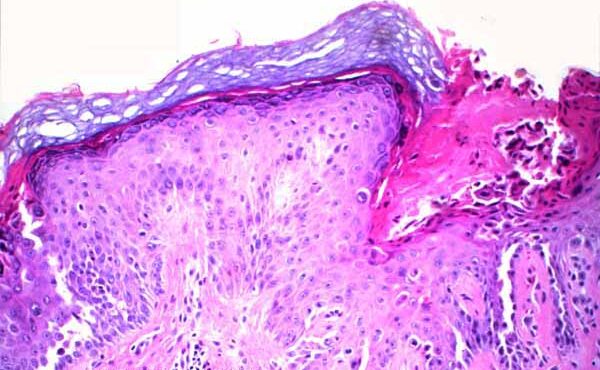

Graft versus Host Disease =داء رفض الطعم للمضيف Graft Versus Host Disease GVHD occurs in situations in which donor immunocompetent T cells transferred into allogenic hosts are incapable of rejecting them. The sources of the T cells include primarily peripheral blood stem cell and bone marrow transplants and, infrequently, unirradiated blood products , solid organ […]